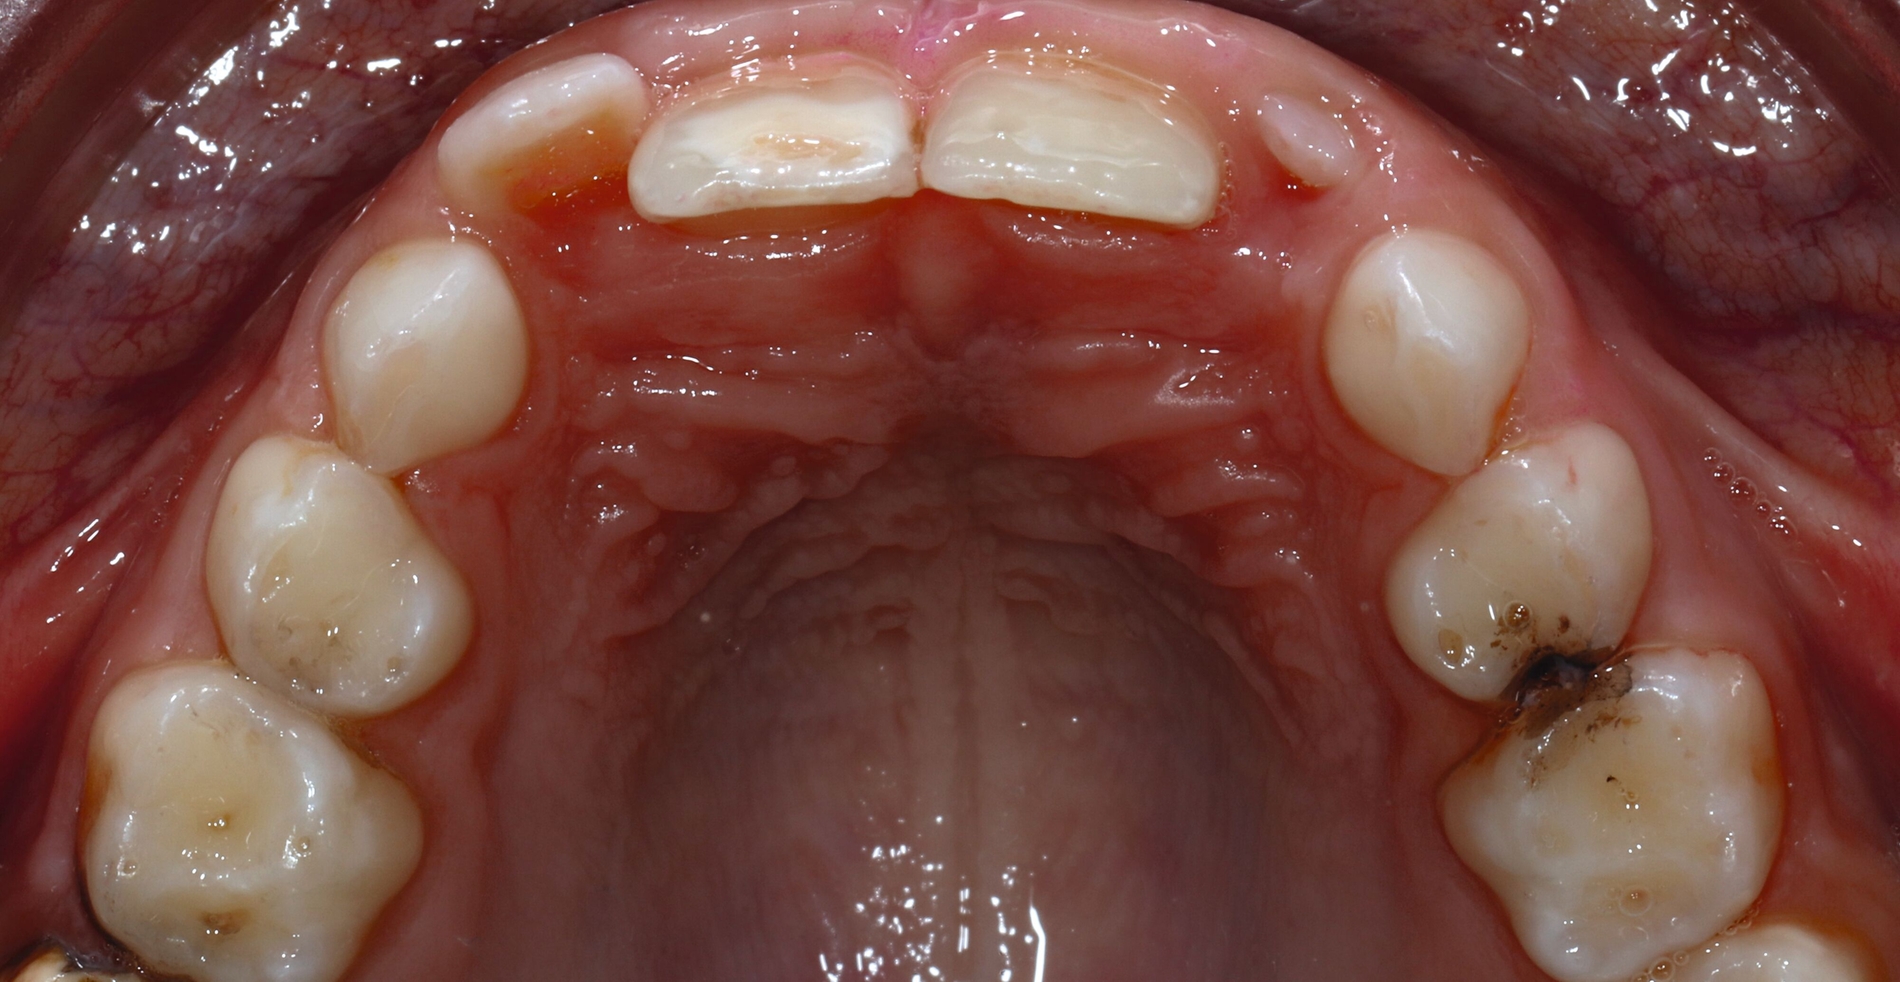

PD Dr. Ruth Santamaría Sanchez (Greifswald) stellte das Greifswalder Kariesmanagementkonzept vor,das die ganze Bandbreite von der Prävention über minimalinvasive Maßnahmen bis hin zur Restauration nach dem aktuellen Stand der Wissenschaft umfasst. Dabei werden klassische Prävention, Kariesinaktivierung (beispielsweise mit Silberfluorid oder Slicing), non- beziehungsweise minimalinvasive Verfahren wie die Hall-Technik sowie klassische Restaurationen und Lückenhalter beziehungsweise Platzmanagement miteinander verzahnt.